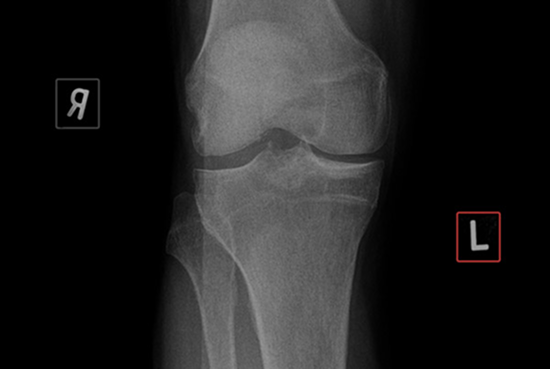

Identify discrepancies in near real time enabling you to take corrective action before the x-ray is reported. RBmarker's RadView module is your co-pilot that can alert you to laterality quality control issues such as:

•  Missing markers - cases where you have simply forgotten to add a digital or lead marker to the x-ray

•  Marker Mismatch - highlight cases where RBmarker has identified possible mismatches between the laterality of the image and the marker used